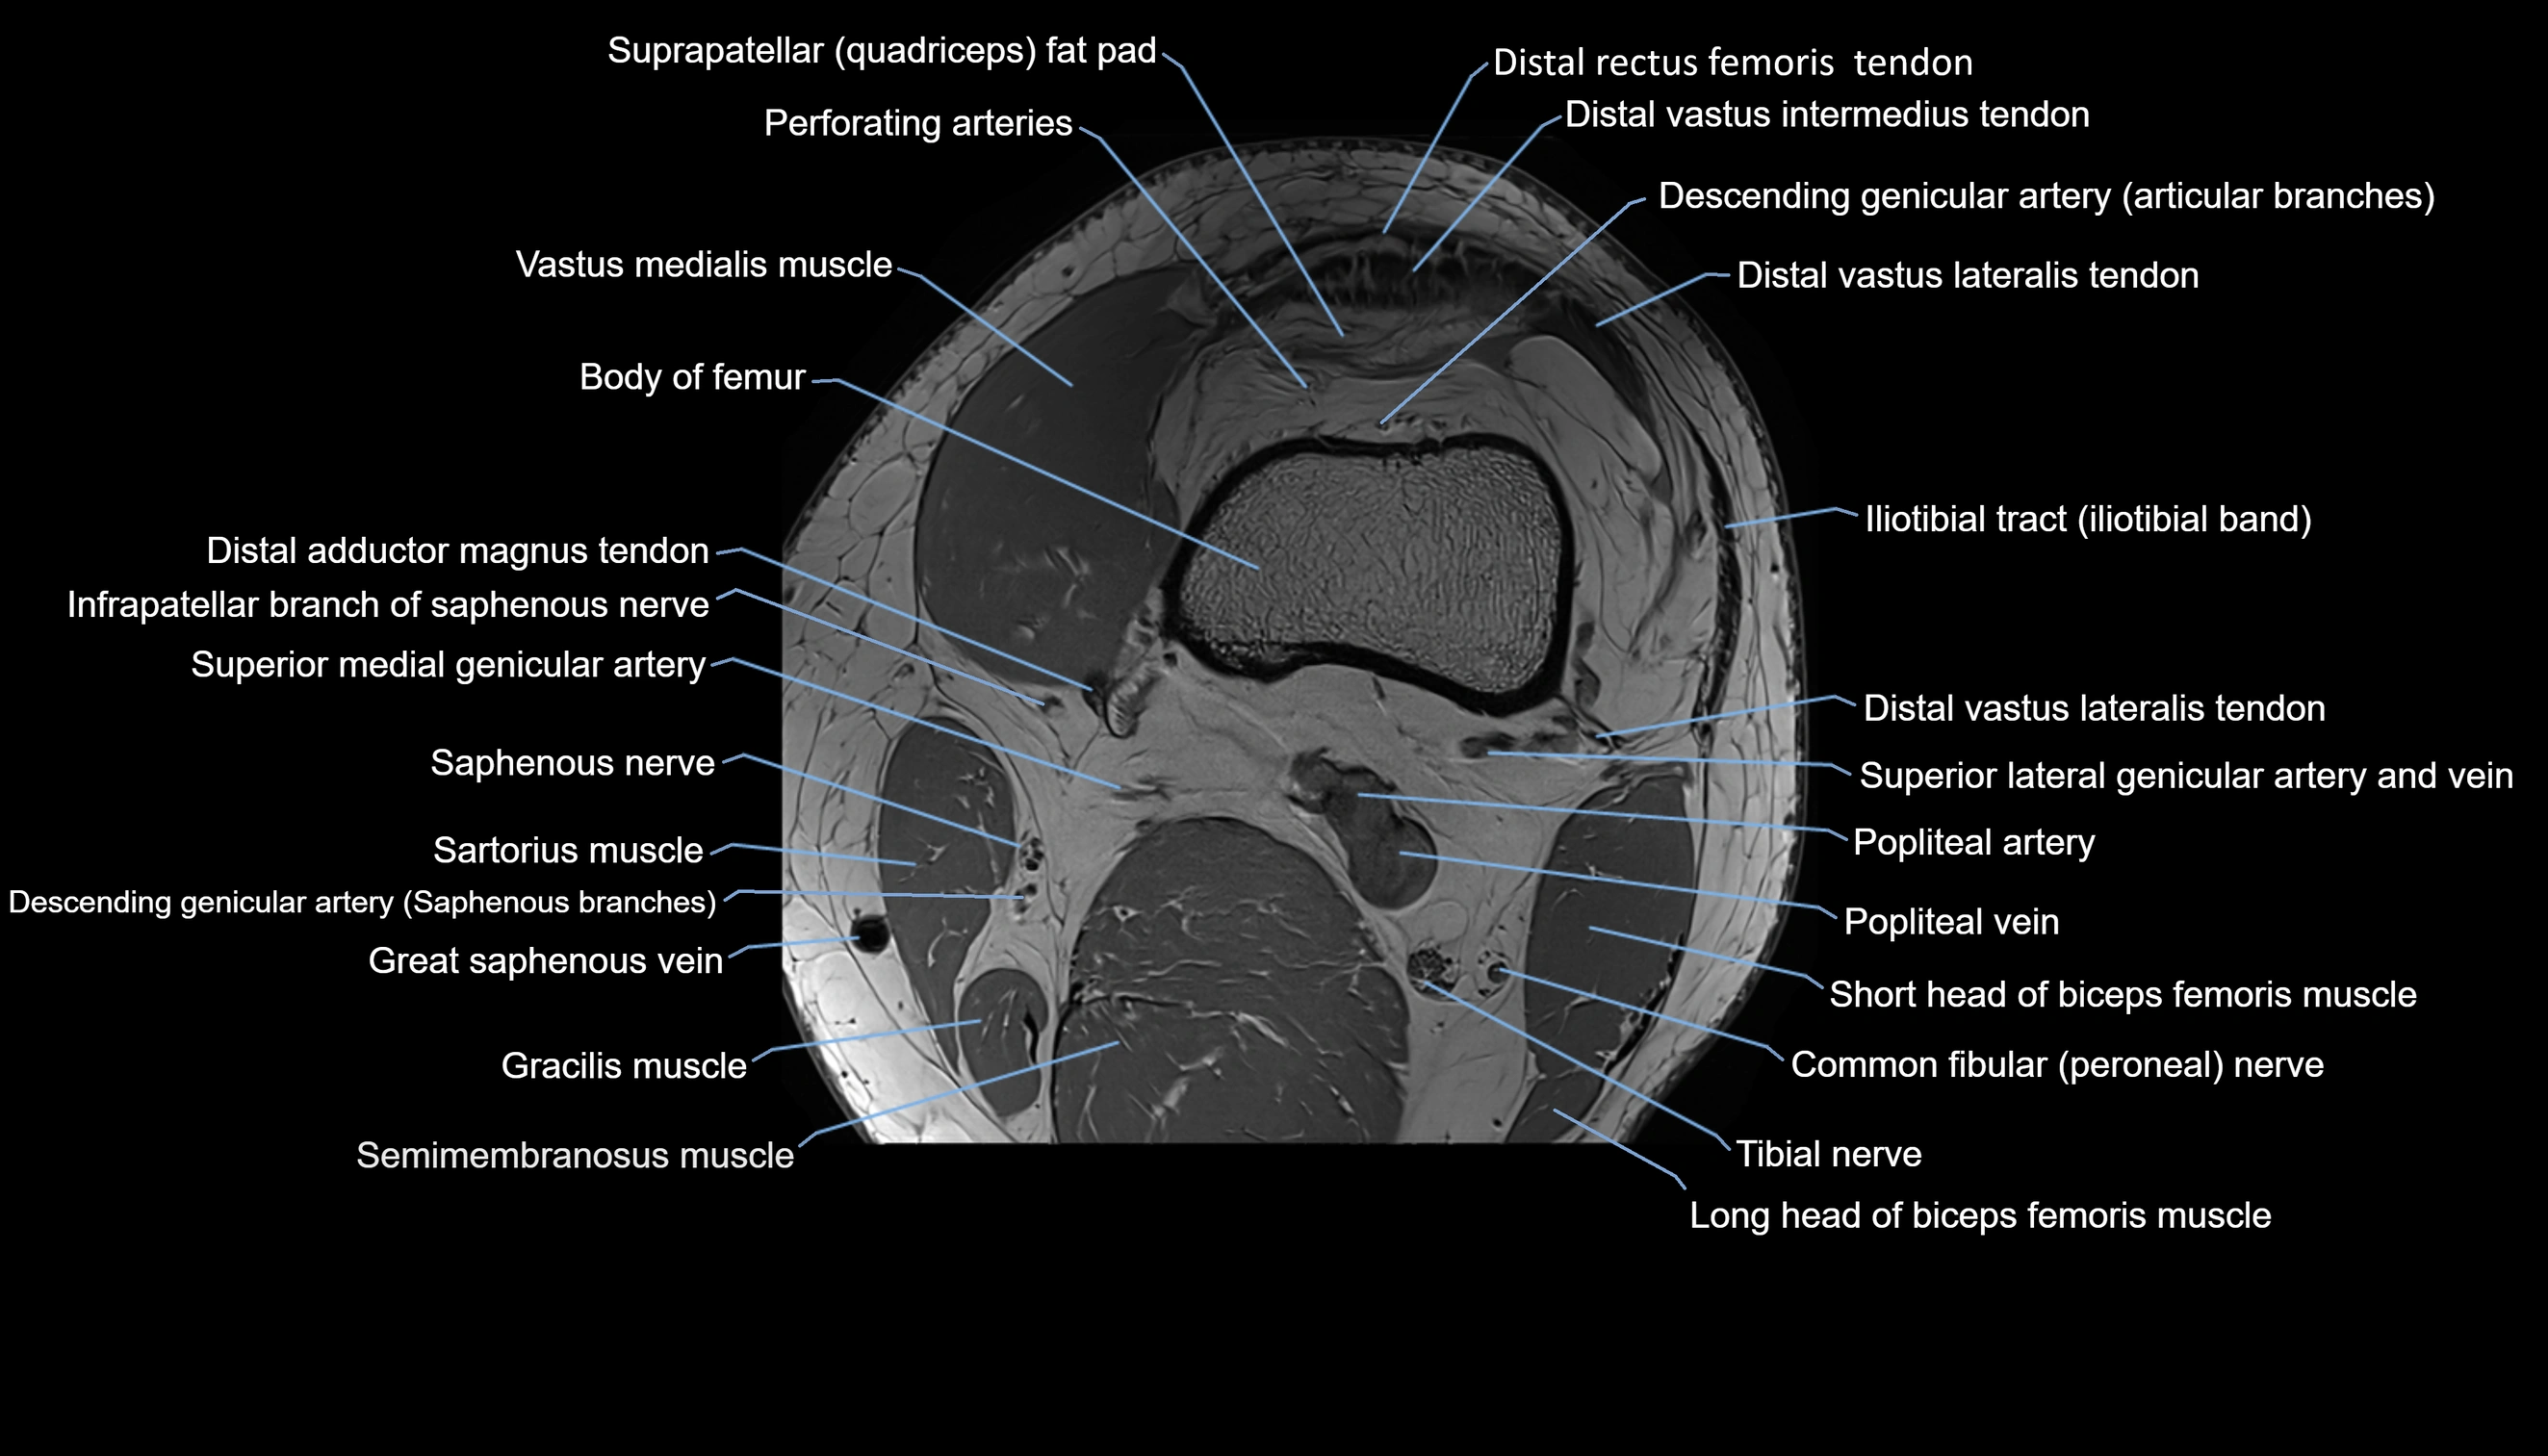

- Body of femur

- Descending genicular artery (Articular branches)

- Descending genicular artery (Saphenous branch)

- Distal adductor magnus tendon

- Infrapatellar branch of saphenous nerve

- Perforating Arteries (Knee joint)

- Popliteal artery

- Popliteal vein

- Saphenous nerve

- Sartorius muscle

- Semimembranosus muscle

- Superior medial genicular artery

- Tibial nerve

- Vastus lateralis muscle

- Vastus medialis muscle

- great saphenous vein